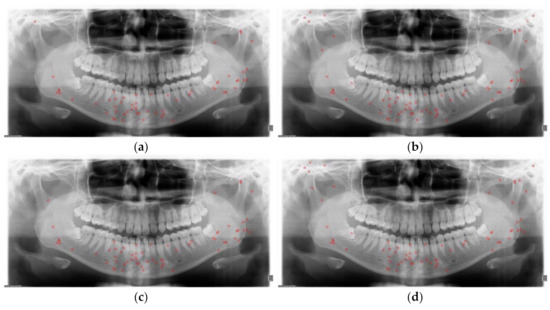

2.2.1. Data Augmentation

3.2. Detection Results